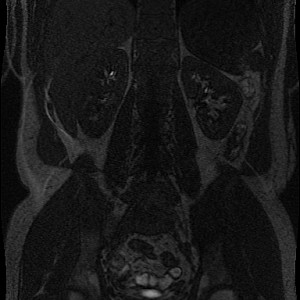

Example of MR Angiography with recording time before and after contrast agent infusion, respectively:

What do we see: Mainly kidneys, liver and and main supporting vessels aggregate contrast agent.